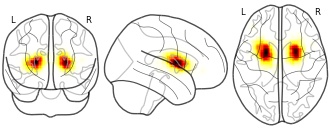

Decoding brain activity using a large-scale probabilistic...

EmailClick to copy linkLink copied Cite(2018). Decoding brain activity using a large-scale probabilistic functional-anatomical atlas of human cognition: topic 169 fwhm=6 [Dataset]. http://identifiers.org/neurovault.image:23423niftiAvailable download formatsUnique identifierhttps://identifiers.org/neurovault.image:23423Dataset updatedJun 30, 2018License

Cite(2018). Decoding brain activity using a large-scale probabilistic functional-anatomical atlas of human cognition: topic 169 fwhm=6 [Dataset]. http://identifiers.org/neurovault.image:23423niftiAvailable download formatsUnique identifierhttps://identifiers.org/neurovault.image:23423Dataset updatedJun 30, 2018LicenseCC0 1.0 Universal Public Domain Dedicationhttps://creativecommons.org/publicdomain/zero/1.0/

License information was derived automaticallyDescriptiontopic_169_fwhm=6.nii.gz

Collection description

GC-LDA topic maps.

Subject species

homo sapiens

Modality

fMRI-BOLD

Analysis level

meta-analysis

Cognitive paradigm (task)

None / Other

Map type

Other